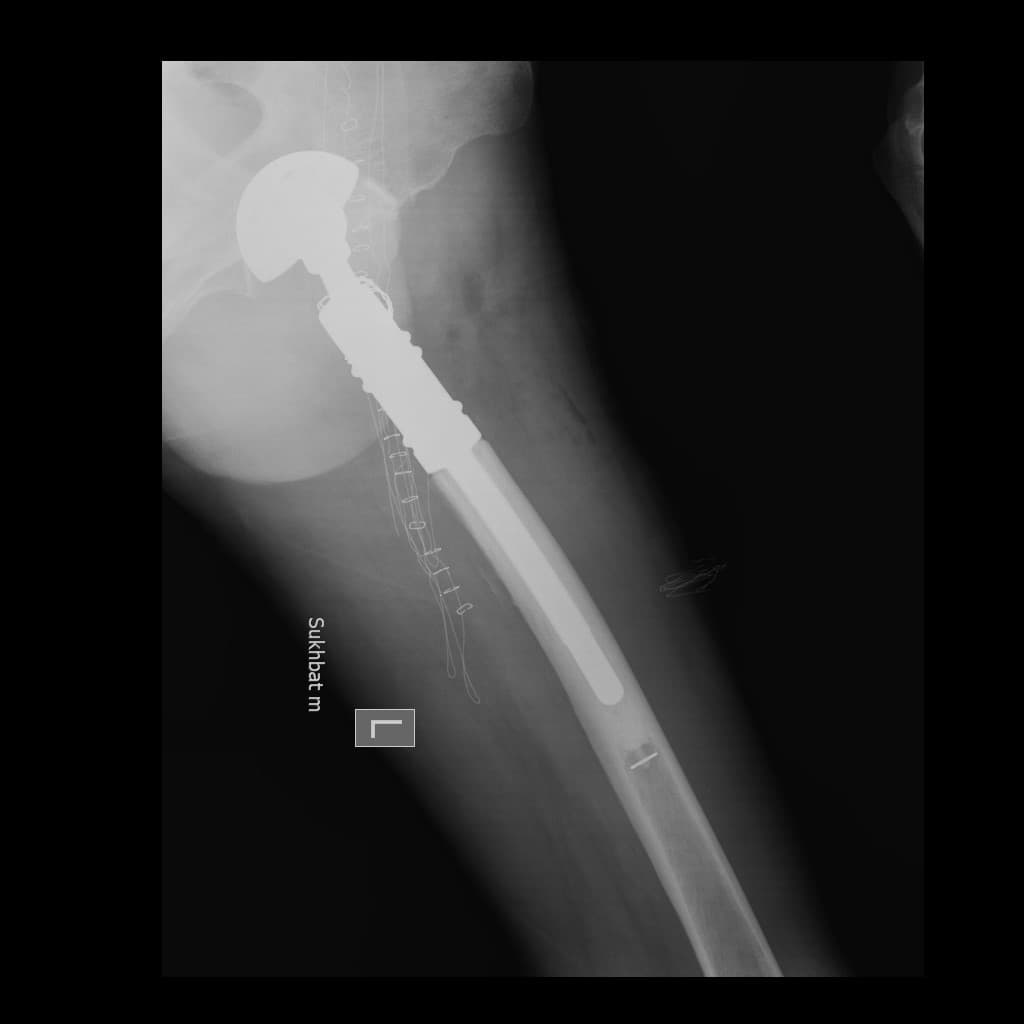

Түнхний толгой хэсгийн цусан хангамжийн алдагдалын улмаас үхжилт өөрчлөлттэй залуу өвчтөнд хүзүү хэсгийн богино шилбэний хиймэл үе суулгах мэс заслын өмнөх болон дараах рентген зураг

Түнхний үе бүтэн солих мэс засал (THA) image5Түнхний үе бүтэн солих мэс засал (THA) image6